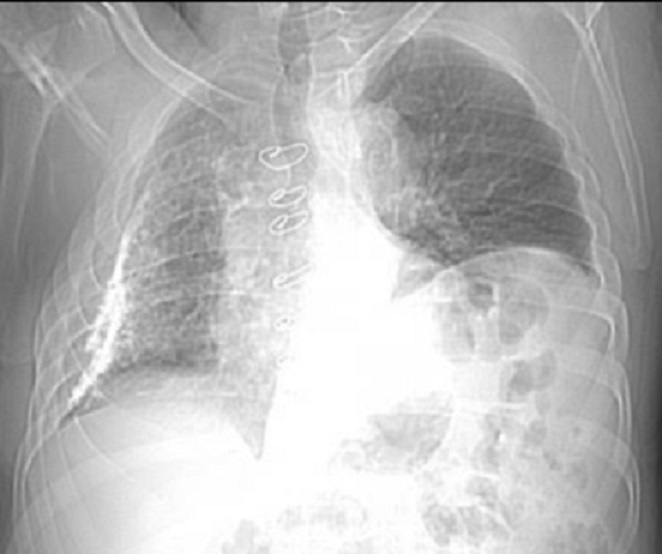

Image

radiologique PA une epaissisement pleural tumorale

d'une epitheloide engio-sarcome de la plevre du

poumon droit . Aspect radiologique est image de

epaissisement diffuse , former par multiple opacite

nodulaire limite tres nette situe de la plevre du

poumon droit |